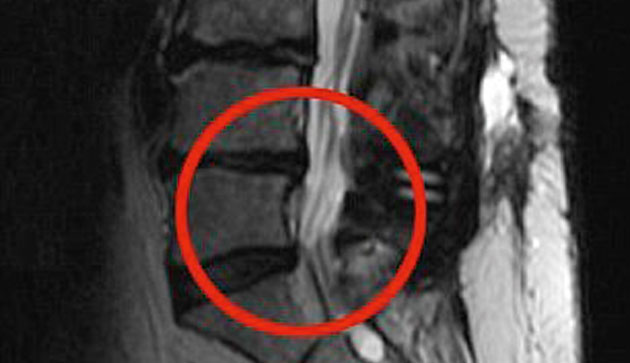

The force of it had ruptured a disc in her spine, leaving her sciatic nerve trapped between two vertebrae.

During a pioneering four-hour operation Victoria, 52, had a titanium cage inserted into her spine to stop the disc from collapsing again.